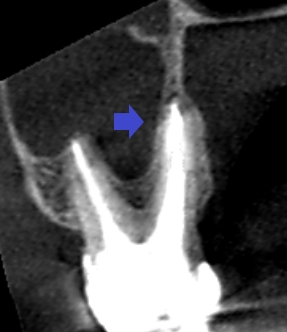

初診時の上顎第二大臼歯の矢状断のCT画像です。

赤い矢印の先に口蓋根をとり巻くような長い膿の影がみられます。歯根破折やと根尖孔外感染が疑われます。